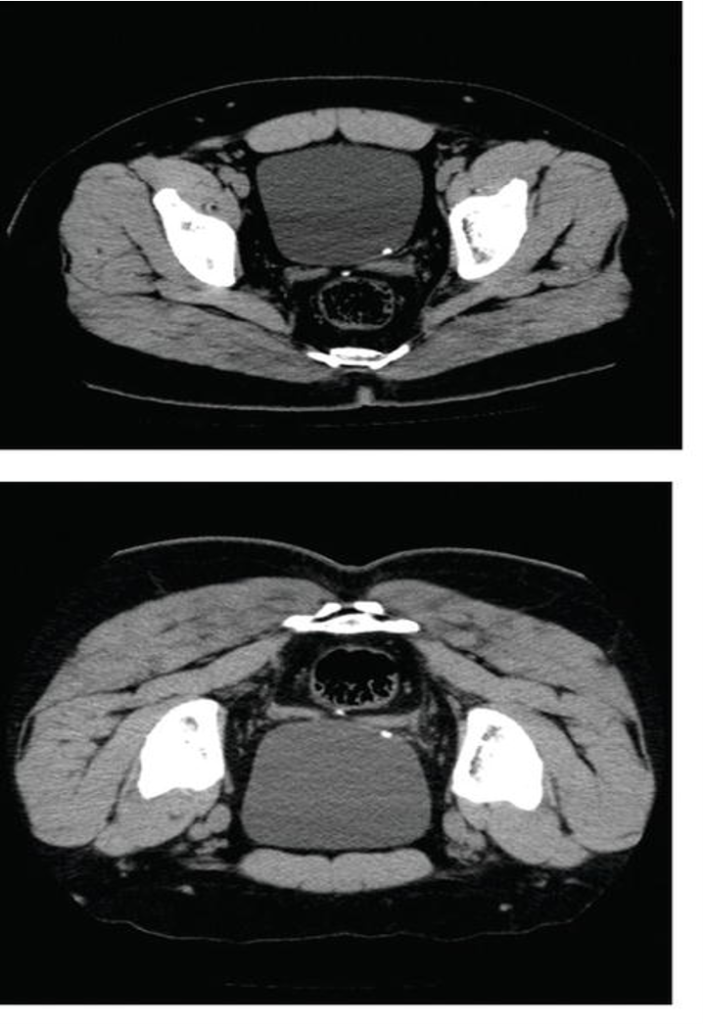

CT KUB axial supine and prone positions demonstrating a left-sided VUJ calculus.